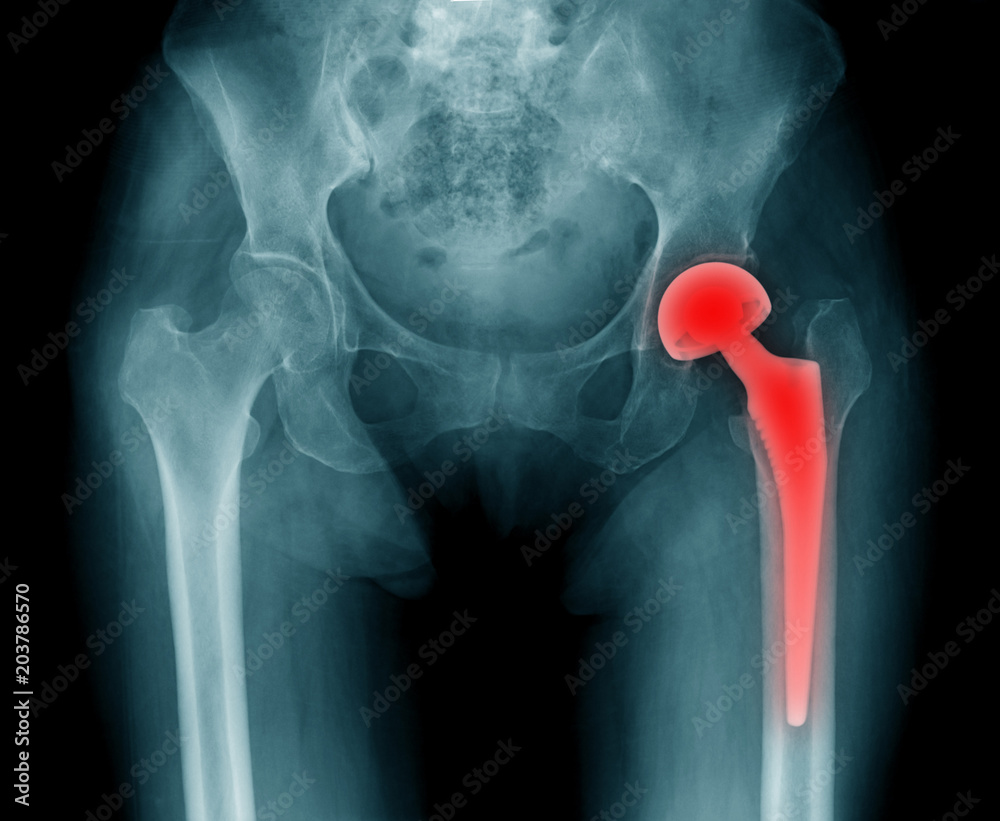

From stock.adobe.com

hip replacement xray, image of radiology hip arthroplasty Stock Photo Adobe Stock Double Hip Replacement Xray If you are having issues with both hips, your doctor might recommend a double hip replacement if you are in good. The artificial hip parts might wear out eventually, especially for people who have hip replacement. A total hip replacement can reduce pain and improve your quality of life, range of motion, ability to walk or run, and enhance or. Double Hip Replacement Xray.